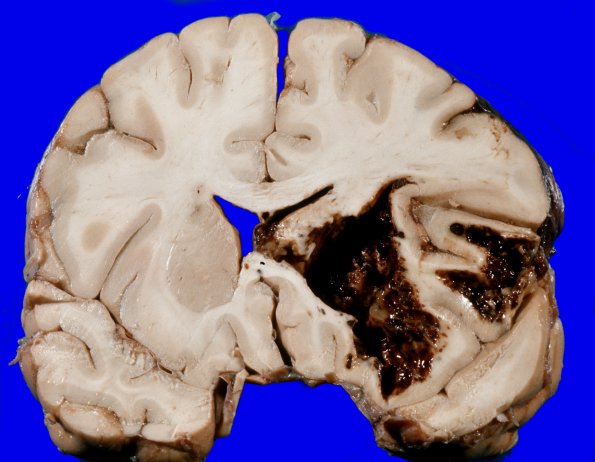

Washington University Experience | NEOPLASMS (HEMATOLYMPHOID) | Granulocytic Sarcoma | 3A1 Leukemic nodules (Case 3) gross 2

Coronal sections through the cerebral hemispheres revealed a large focus of hemorrhage with adjacent hemorrhagic necrosis in the left frontoparietal region measuring approximately 5 x 4 x 2.5 cm. Surrounding the margin of the hemorrhagic necrosis there were multiple punctate focal hemorrhagic lesions with a center measuring up to 0.5 cm. in diameter. There was evidence of a midline cerebral hemispheric shift, with compression of the left lateral ventricle and displacement of the septum pellucidum in the absence of cingulate gyrus herniation